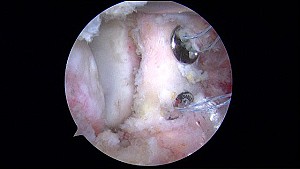

Foto chirurgia trapianto

L’entusiasmo per questa nuova metodica si è inoltre accompagnato alla diffusione di ulteriori varianti di tecnica artroscopica, in particolare con l’utilizzo di sistemi di fissazione alternativi (bottoni corticali e fili ad alta resistenza), con l’obiettivo di ottenere una fissazione ancora più accurata e stabile della coracoide riducendo le complicanze legate all’hardware (Fig.1).